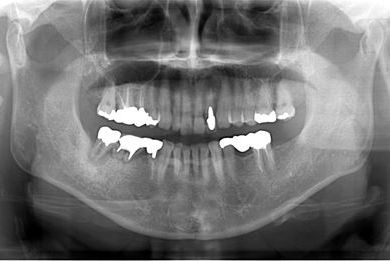

インプラントの症例写真 IMPLANT

骨再生スピードインプラント治療+セラミック治療

| 性別/年齢 | 女性 / 58歳 | ||||||||||||||||||||||||||||||||

| 主訴 | 左上前歯となりがゆらついている。他院でインプラントが必要と言われ、相談に来ました。 | ||||||||||||||||||||||||||||||||

| 治療方針 | 骨再生法によりインプラント治療を可能にする。抜歯と同時にインプラント埋入を行い、治療期間を短縮する。 | ||||||||||||||||||||||||||||||||

| 治療内容 | インプラント3本(抜歯即日スピードインプラント、GBR)、メタルボンドセラミッククラウン1本、ハイブリッドセラミッククラウン4本(ハイブリッドセラミック用土台1本) | ||||||||||||||||||||||||||||||||

| 総治療費 | 1,655,326円 | ||||||||||||||||||||||||||||||||

| 治療期間 | 1年3ヶ月 |